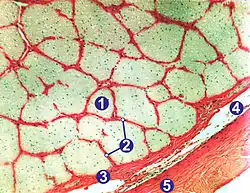

Гістологічна організація волокон

.jpg.webp)

2) Периневрій;

3) М'яка оболонка;

4) Павутинна оболонка та підпавутинний простір;

5) Тверда оболона.

Товщина нервових волокон (аксонів) нерва становить в середньому 10 мкм, середня кількість їх в одному нерві — півтора мільйона. Волокна преламінарної та ламінарної частин формують пучки та не покриваються мієліном; він вперше з'являється у ретроламінарній частині. Мієлін зорового нерва є центрального походження, тобто виробляється олігодендроцитами, що є ознакою того, що зоровий нерв є радше частиною ЦНС, ніж ПНС. У цих же ділянках волокна оточені астроцитами.[43][45][46] Вони відокремлюють нерв від тканини склери у ділянці решітчастої пластинки, утворюючи мембрану Джейкобі[47].

Така мікроанатомічна організація характерна для інших частин зорового нерва: формування пучків нервових волокон, які оточені астро-, мікро- та олігодендроглією[43][46].